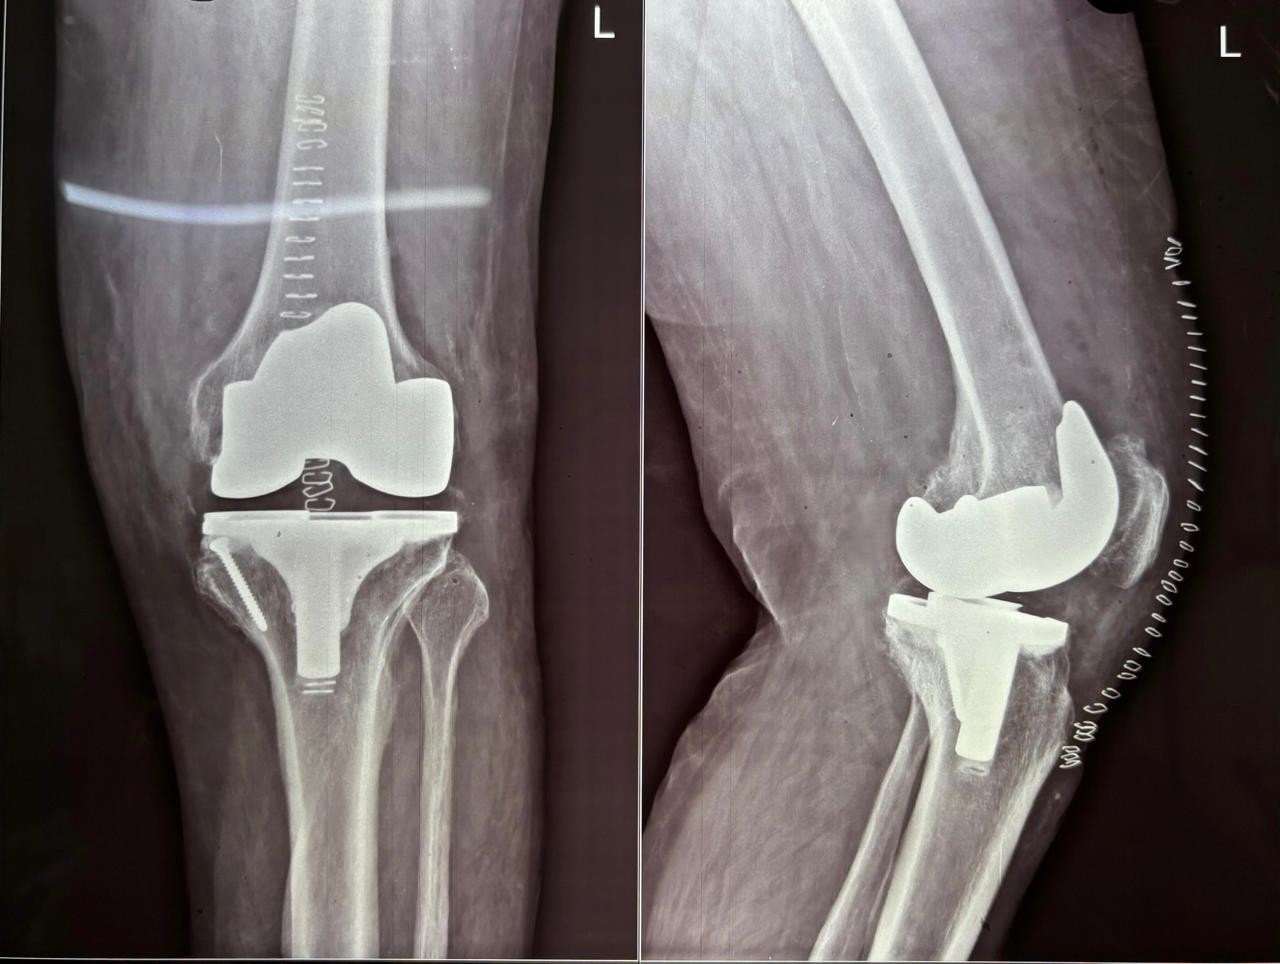

Post-Op X-Ray

Post-Op Follow Up